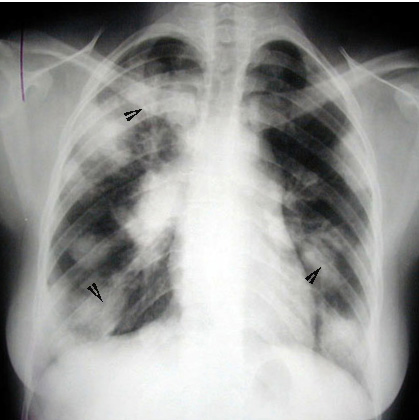

Large nodules with air bronchogram (arrowheads).

Bilateral hilar and paratracheal adenopathy.

Appearance often mistaken for metastatic disease.